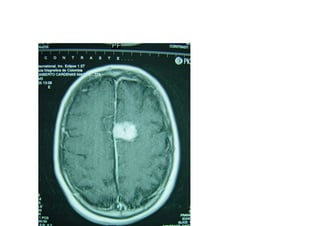

Neoplasica